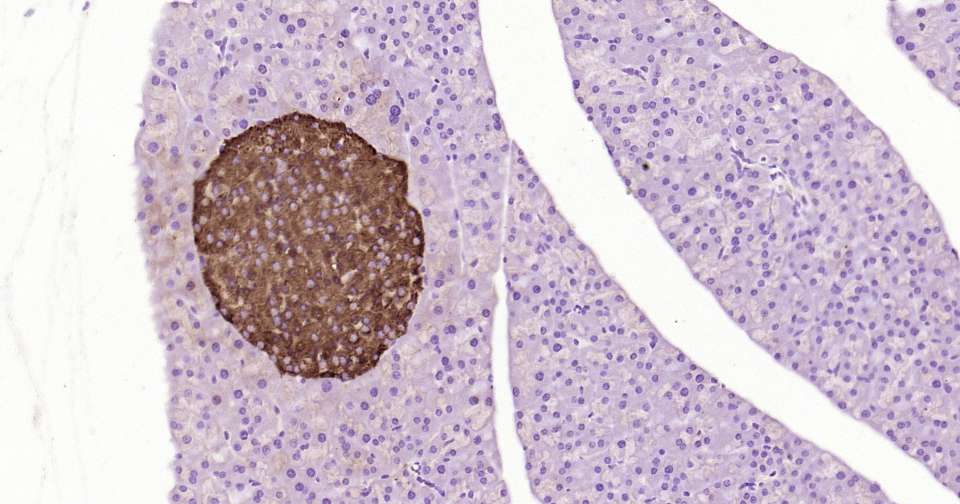

Immunohistochemical analysis of paraffin embedded rat pancreas tissue slide using IHC0364R (Rat Notch1 Kit).